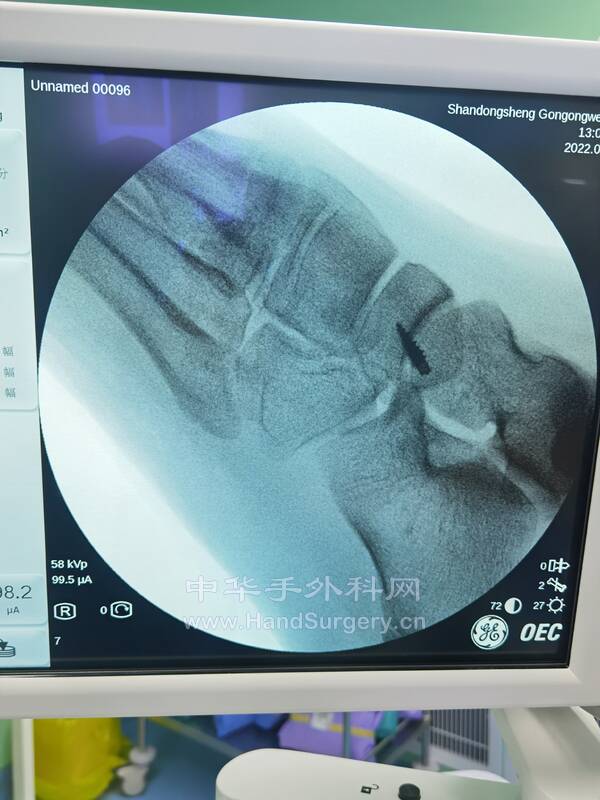

1.副舟骨损伤(图2-6),胫后肌腱止点重建术,手术要点:

选择足背内侧舟骨突起处纵行小切口,长约3cm,显露至骨膜,找到副舟骨,将其完整切除,舟骨内侧缘用咬骨钳咬除关节面,至接近正常舟骨形状,选直径3.5mm的铆钉垂直于骨面拧入,在铆钉两侧用直径1.2mm的克氏针平行贯穿打孔,用圆针缝入2-0(或3-0)可吸收线,连同铆钉缝线编织缝合胫后肌腱止点,闭合切口,术后石膏固定。